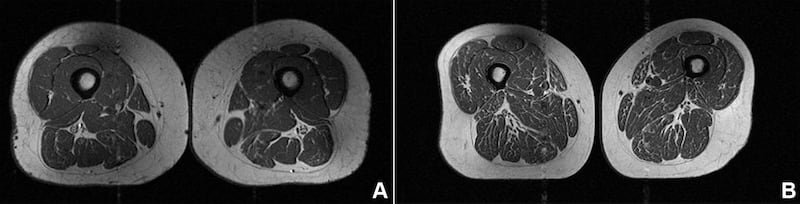

The image looks like a slice of highly marbled flesh, reminiscent of a high-end steak with abundant fine-grained streaks of fat. But that’s not dinner. It’s an MRI scan of the thigh of a 62-year-old woman who obtained 87 per cent of her annual calories from ultraprocessed food.

A 61-year-old woman in the study also had fat marbling in her thigh muscles, but it was not as intense. About 29% of her annual diet consisted of ultraprocessed foods.

The 61-year-old woman with a diet consisting of 29.5% ultraprocessed food (A in image below) had a slightly higher BMI of 32.6 and a much lower activity score than the woman (B in image) with a BMI of 31.8 whose diet was 87.1% ultraprocessed. Yet the woman with the higher ultraprocessed score still had dramatically more fat marbling in her thighs.